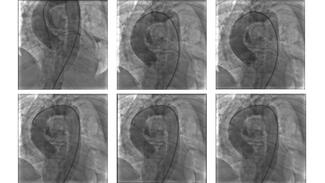

Kewal Kanabar, MD; Pooja Vyas, MD; Karthik Natarajan, MD; Nirmal Shah, MD; Radhakishan Dake, MD

A 50-year-old female patient presented with class III angina for 6 months, positive stress test, and a prior CT angiogram suggestive of three-vessel disease. Coronary angiogram showed disease of the distal ramus intermedius, proximal...